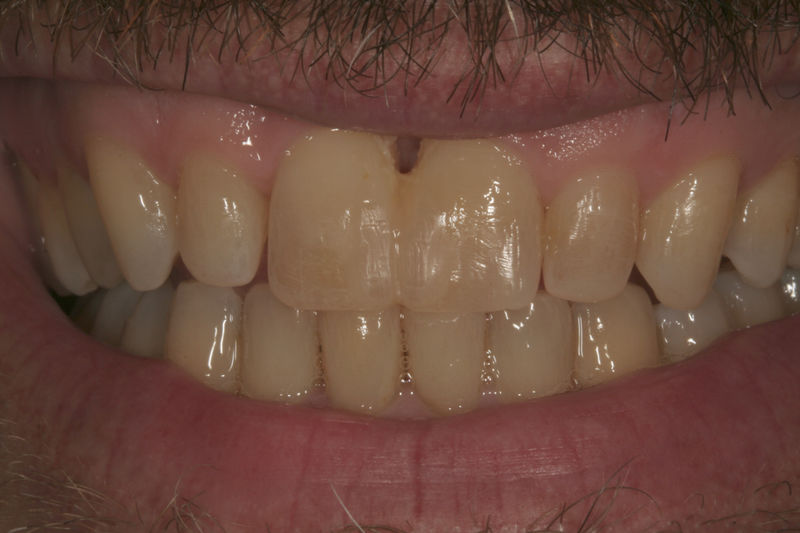

Amplia gama de tratamientos para mejorar la apariencia de la sonrisa, corrigiendo el color, la forma, el tamaño, la alineación y la posición de los dientes. Los procedimientos más comunes y solicitados incluyen el blanqueamiento dental, las carillas y coronas, así como las resinas.

Implantes, ortodoncia y coronas.

Ortodoncia y coronas.

Cirugía ortognática, implantes, carillas y coronas,